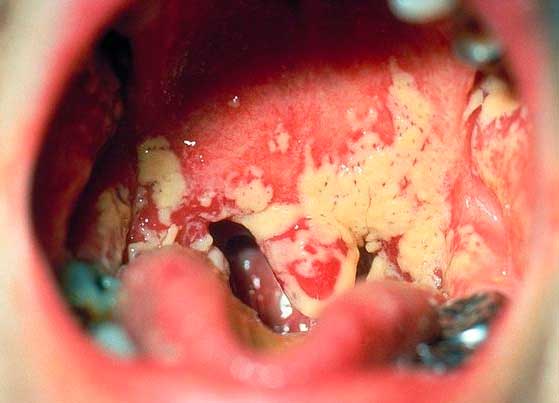

Изображение показывает горло пациента, у которого была обнаружена катаральная ангина без повышения температуры:

При данном заболевании температура тела больного обычно немного повышается относительно обычной, но остаётся в пределах субфебрильных значений — от 37,0°С до 37,5°С. Часто её не замечают, когда кладут руку на лоб, и даже при измерении термометром не придают этому особого значения.

В то же время обычная катаральная ангина является серьезным заболеванием, которое требует применения антибиотиков для лечения. Без правильной терапии она может превратиться в гнойную форму или вызвать различные осложнения, начиная от хронического тонзиллита и заканчивая ревматизмом и даже заражением крови.

У взрослых обычно болезнь в катаральной форме проходит более легко, в то время как у детей реже встречается типичная ангина без повышения температуры.